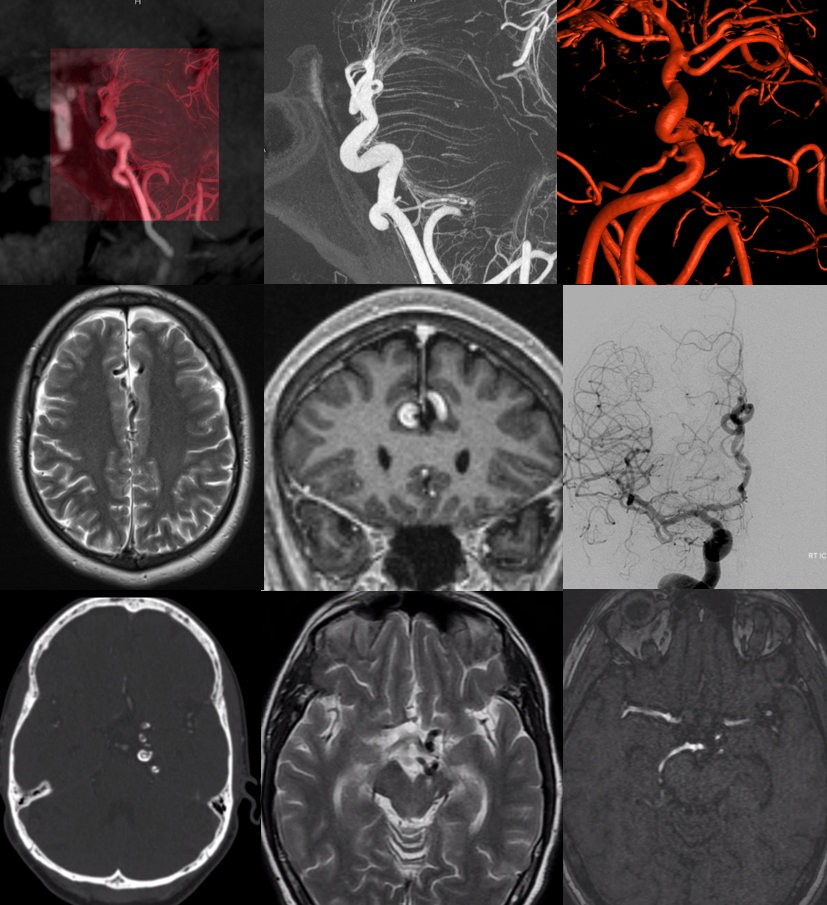

Case 1 — chronic headaches, normal exam. MRI reading was suspected AVM — except there are no dilated veins

Calcification on susceptibility imaging

Subtle adjacent cortical dysplasia

Same on coronal T1 post

Typical angio appearance — tortuous, fusiform A2/Pericalossal, without arteriovenous shunting